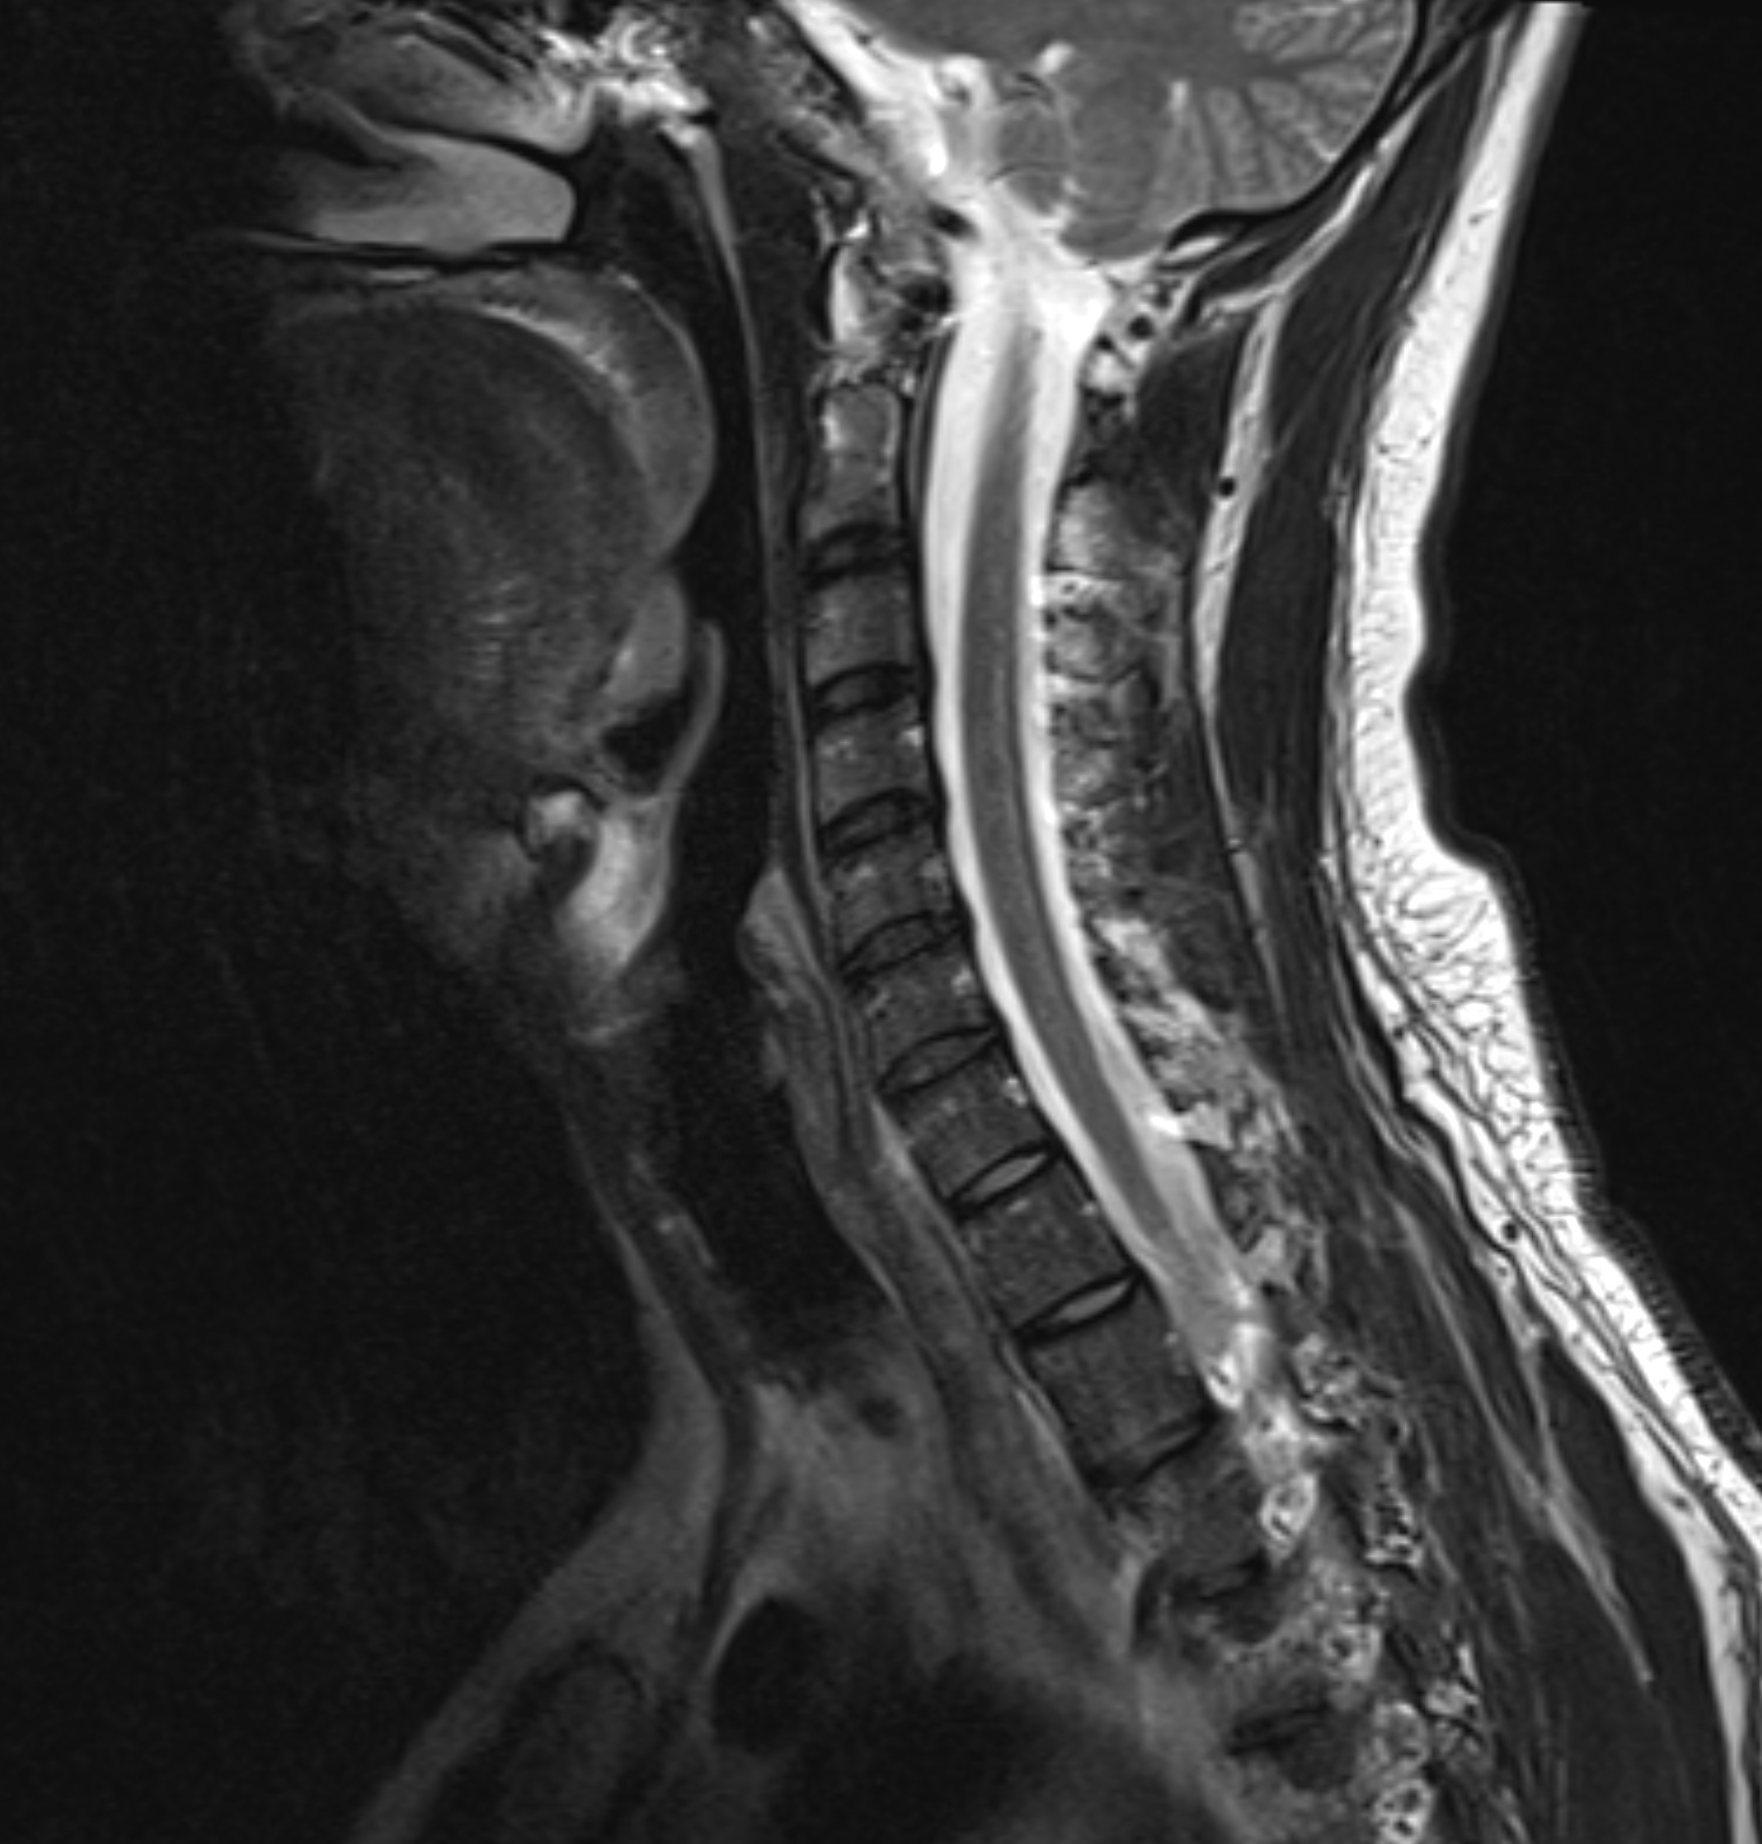

Undersökningen ger noggranna bilder av halskotor, diskar, ryggmärg, nervrötter och omgivande mjukdelar. Eftersom MR inte använder röntgenstrålning är den lämplig även för upprepade undersökningar eller för patienter där strålningsfrihet är extra viktigt.

Smärta i nacken som strålar ut i axlar, armar eller fingrar kan tyda på tryck mot nervrötter i halsryggen. Även stelhet, domningar, svaghet eller balansproblem kan ha sitt ursprung i förändringar i halskotpelaren. MR halsrygg är en skonsam och mycket detaljerad bilddiagnostisk metod som används för att kartlägga orsaker till dessa symtom – oavsett om de beror på diskbråck, artros, spinal stenos eller inflammation.